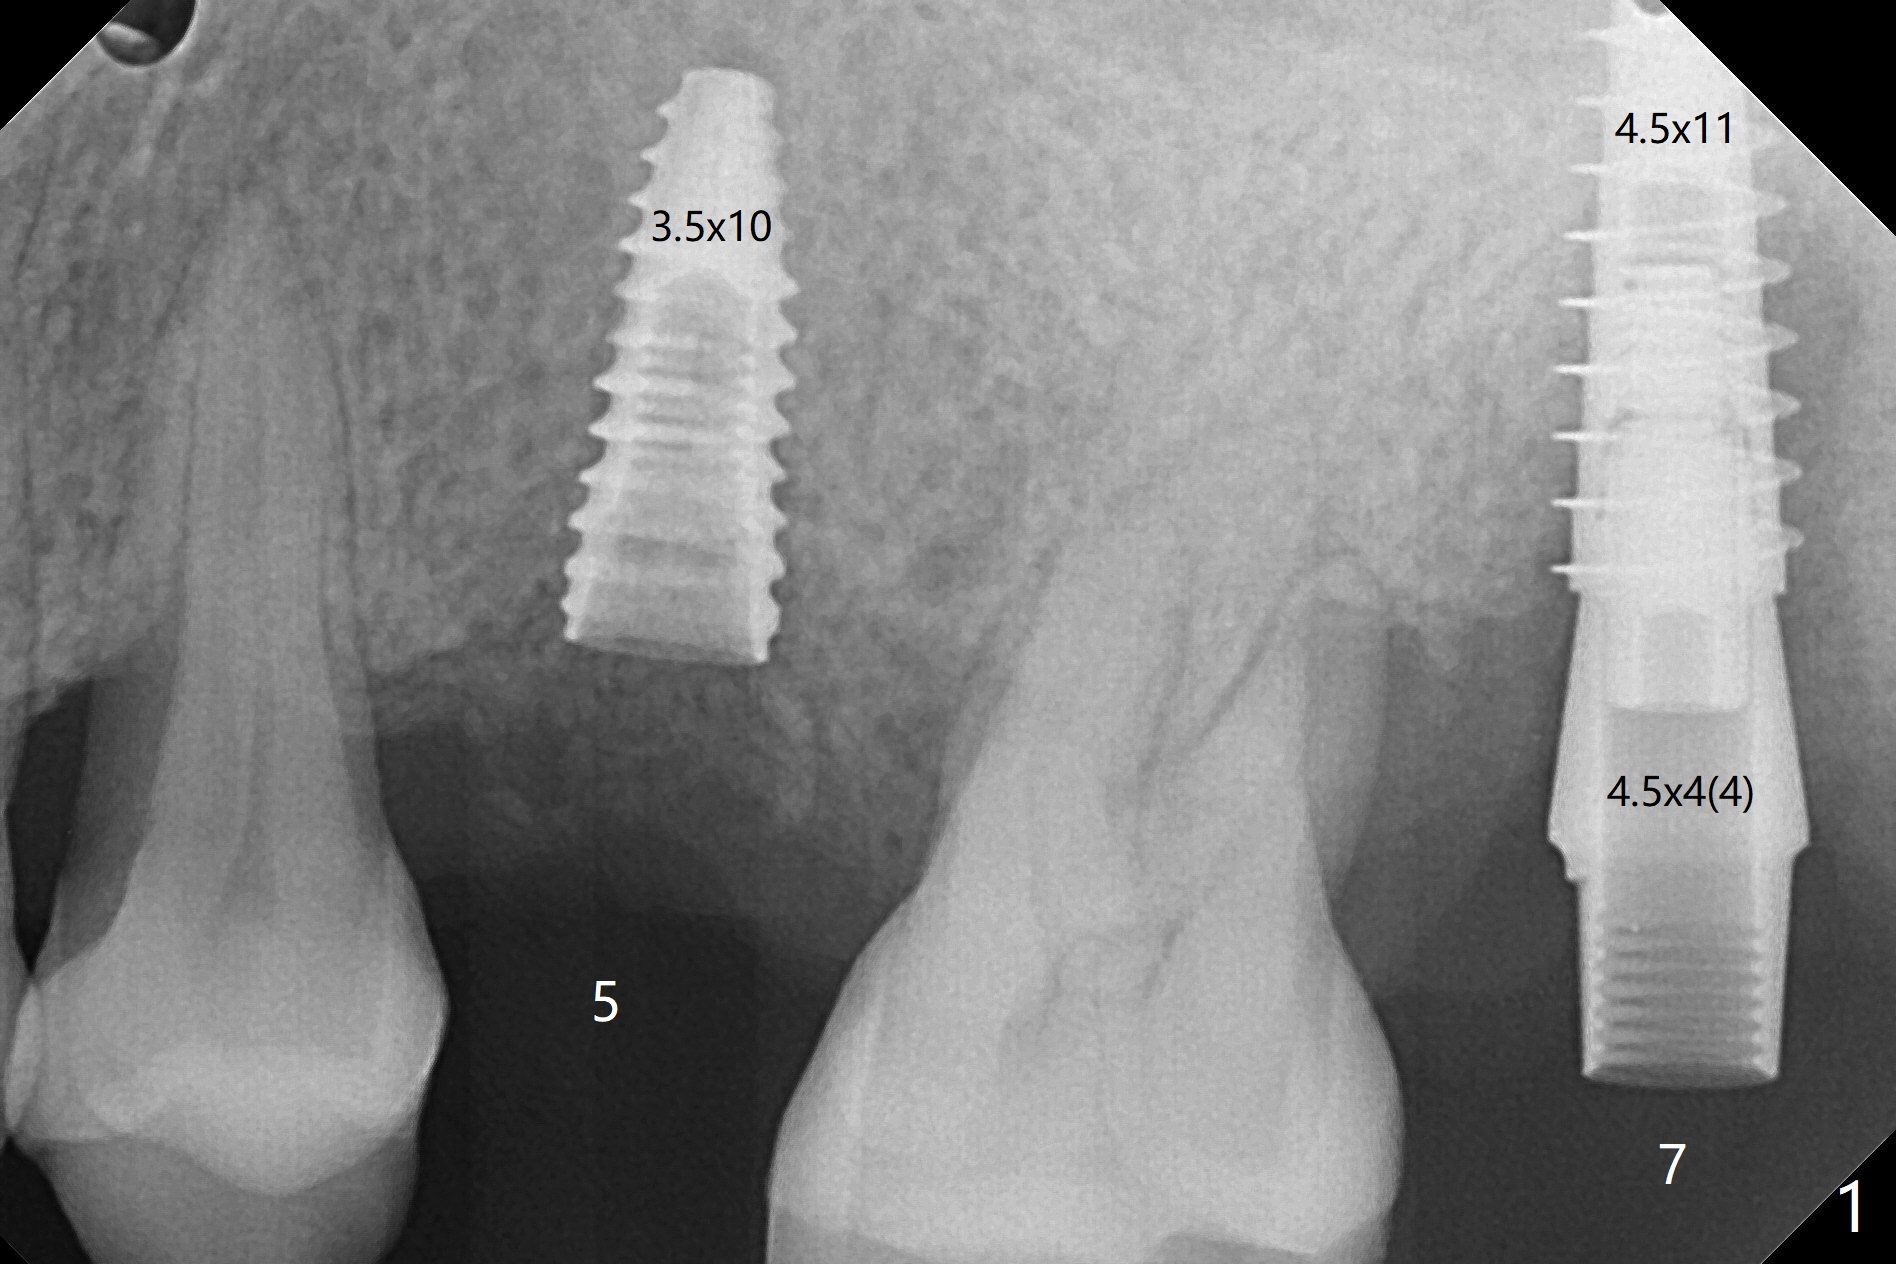

左上5延期植体扭力很高(50 Ncm,图一),而7(即刻)低(~15 Ncm),放置粘性骨粉后(图二:*),制作临时牙冠,长植体尚未穿过上颌窦底板(图三:红虚线)。